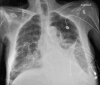

Clostridium difficile (CD) is a spore-forming, Gram-positive anaerobic bacillus that causes toxin-mediated mucosal injury leading to pseudomembranous colitis, clinically characterized by diarrheal disease. Ascites is an infrequent manifestation in severe or fulminant CD colitis. The pathogenesis of ascites in CD colitis is poorly understood but includes hypoalbuminemia due to protein-losing enteropathy, transmural inflammation, toxin-mediated capillary leak, colonic perforation, and concomitant diseases. We report the case of a middle-aged woman who presented with an opioid overdose and subsequently developed severe CD colitis. The infection was complicated with low serum-ascites albumin gradient (SAAG), high protein, culture-negative, neutrophil-predominant ascites, devoid of visceral perforation, or an alternative etiology for ascites. Treatment with oral vancomycin and intravenous metronidazole led to the complete resolution of symptoms and ascites. This case highlights an uncommon presentation of a common healthcare-associated infection and reinforces the importance of recognizing atypical manifestations of CD. While there are no specific management guidelines for this subset, treating the underlying colitis appears sufficient to resolve the ascites in most cases.